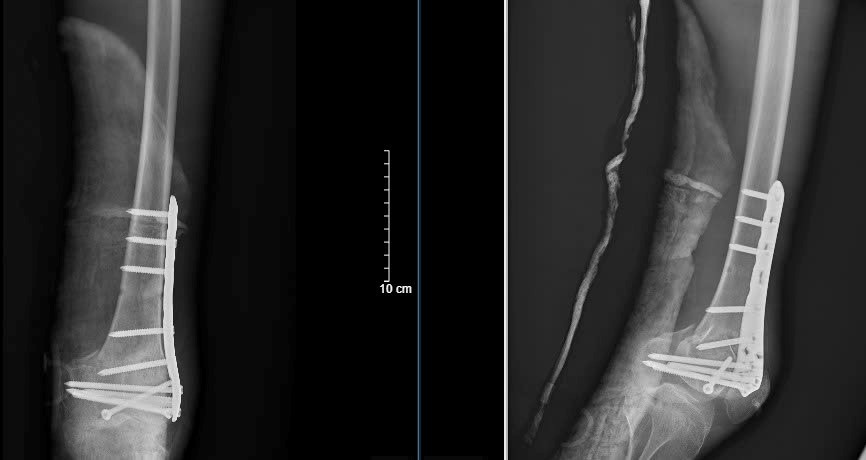

Hình ảnh Xquang sau phẫu thuật